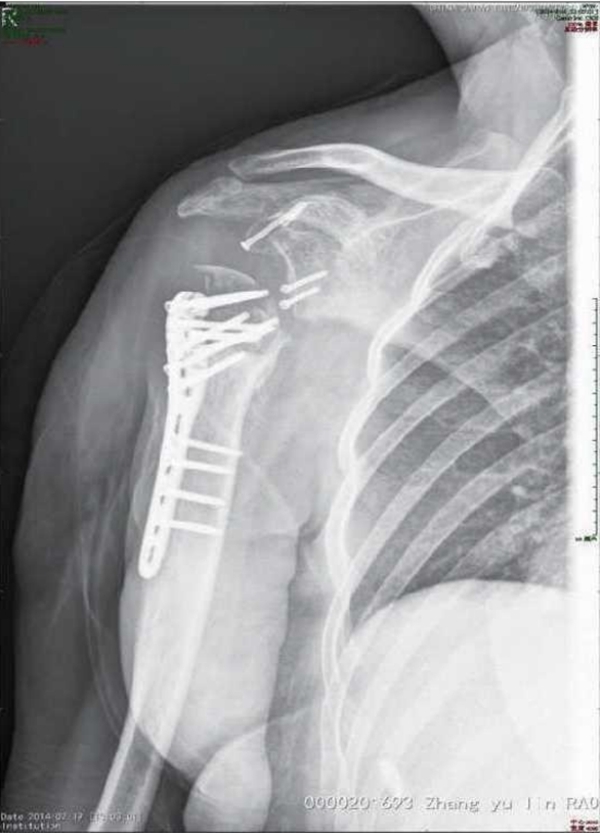

肱骨近端骨折内固定术后整体并发症发生率为30%。其中,常见的并发症主要有螺钉切出/穿透关节面、肱骨头内翻畸形、肱骨头缺血坏死、髓内钉移位、骨折不愈合、内固定断裂等(图1~3)。

图3 肱骨近端骨折逝内钉内固定术后内固定移位